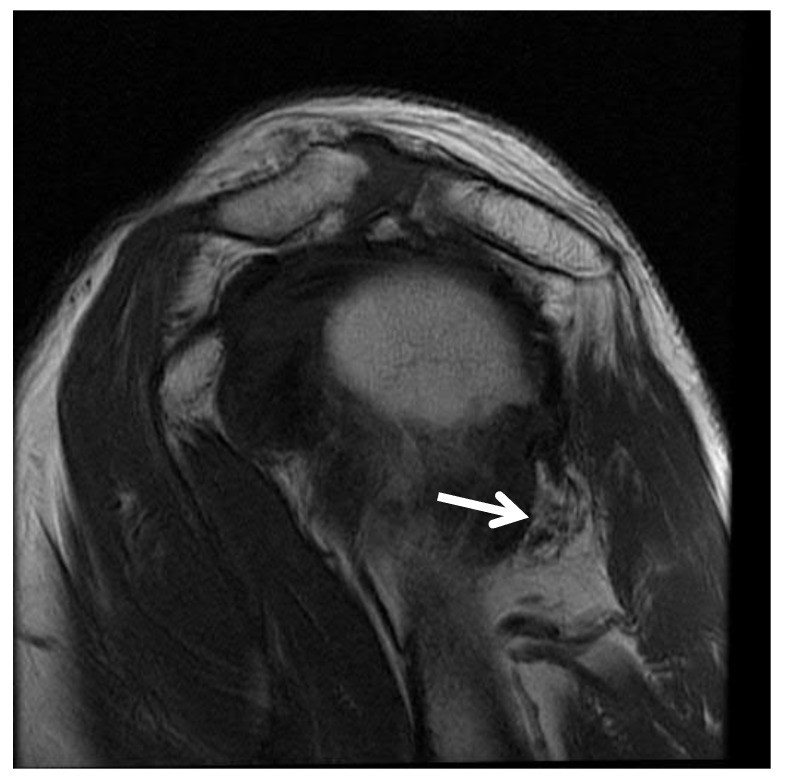

数字减影血管造影、计算机断层血管造影和磁共振血管造影都被用于显示PHCA闭塞。虽然没有QSS的“金标准”诊断测试,但磁共振成像(MRI)通常是成像的首选。MRI常显示小圆肌局灶性脂肪萎缩,可排除肩痛的病理原因。动脉造影被描述为QSS诊断的基石;它被用来显示当病人的手臂处于外展和外旋时PHCA的压迫。与病理性肩关节相比,双侧上肢动脉造影有助于建立患者的基础健康解剖结构。PHCA流出减少表明邻近腋神经受压导致QSS。然而,在一项对照研究中,80%的无症状对照者在动脉造影中显示PHCA闭塞。

四边孔综合征患者肩关节磁共振成像左小圆肌萎缩。